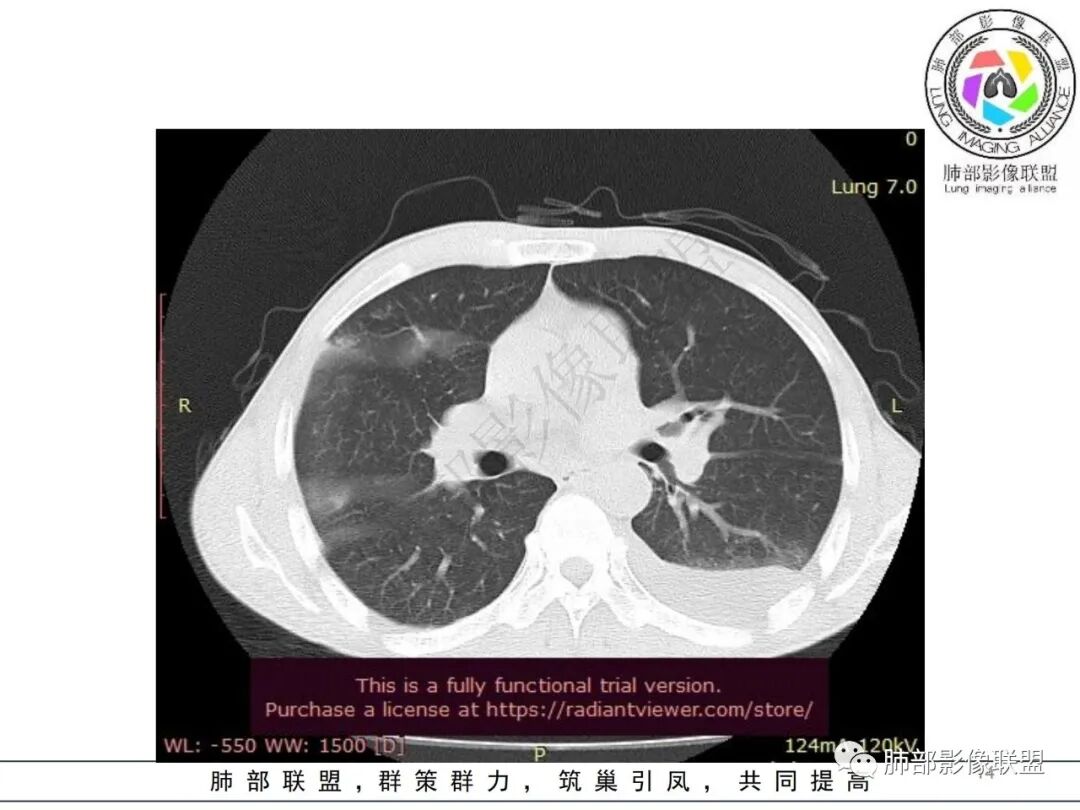

影像表现:双肺弥漫分布斑片影、实变影、磨玻璃影、结节影,晕征、反晕征,随机分布,部分病灶空洞形成前兆,左侧胸腔积液。

两肺多发斑片状实变影,周围GGO

主体还是沿支气管,大片叶段性分布

影像上急性感染,大叶性病变为主

单凭影像:鹦鹉热、军团要考虑,因为内部无坏死,非典型气道为主

我纠结的是,这是气道来源还是血播,如果血播加上海南下田,优先类鼻疽,如果气道,军团也要考虑,只是没见过军团反晕,除非免疫缺陷,混合感染。另外肺克,肺克好像气血皆可,后面反晕出洞,如果没有海南,也要考虑吧,肺克也是免疫妥协相关菌

早上这里是支持血播的

这些层面又像气道

这一类表现等于是病灶没有沿气道趋势,不支持以肺实质、支气管的分布区域,我认为是沿气道到播散,间质蔓延为主

这是比较早的病灶,其他的比较晚的病灶

觉得后面那些符合血道,左下的更符合气道的

目前大家支持的观点:肠道来源,肺血播,累及气道

常规分析:左侧胸水,左下肺病灶大,周围渗出明显,气道壁增厚,内部还无坏死,复查坏死空洞也小

从复查分析,按常规左下病灶比其他大,发病早,应该早空洞,更大才对

现在影像反而空洞小,而且早就累及气道,似乎不大符合常规

影像表现:双肺多发结节、实变影,大部分病灶边界不清,随机分布趋势,左下肺“反晕征”,似有形成空洞趋势。左侧胸腔积液。治疗后复查 ,大部分病灶吸收好转,呈较为典型血播分布,肝脏低密度块影,边界不清,符合肝脓肿。

综合分析:结合症状及实验室检查,均提示本例为感染性病变;海南居住史首先会让我们考虑是否为类鼻疽,类鼻疽主要为血道播散,此时判断病灶为气道还是血道有重要鉴别意义。首次检查片分析气道、血道均有,没有薄壁气囊,结合临床PCT等实验室检查,肺炎克雷伯杆菌感染的可能性增大。复查片显示肝脓肿,加之糖尿病,临床诊断趋于明朗化。血培养及痰培养均可见肺克雷伯杆菌,诊断明确!